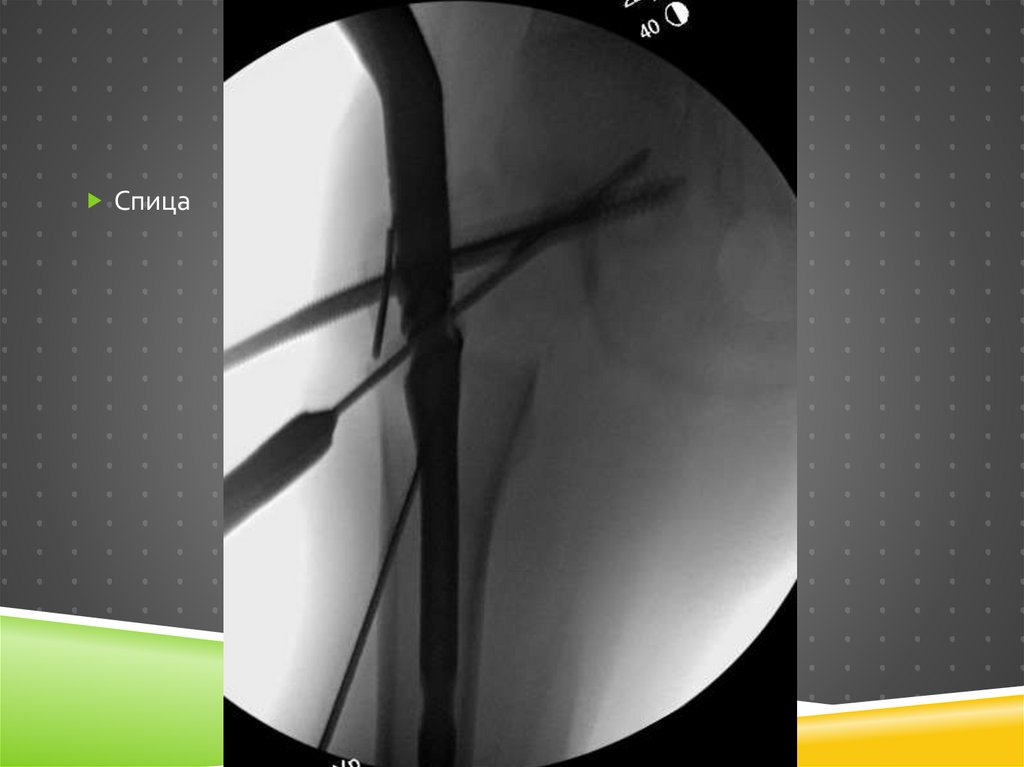

Спица